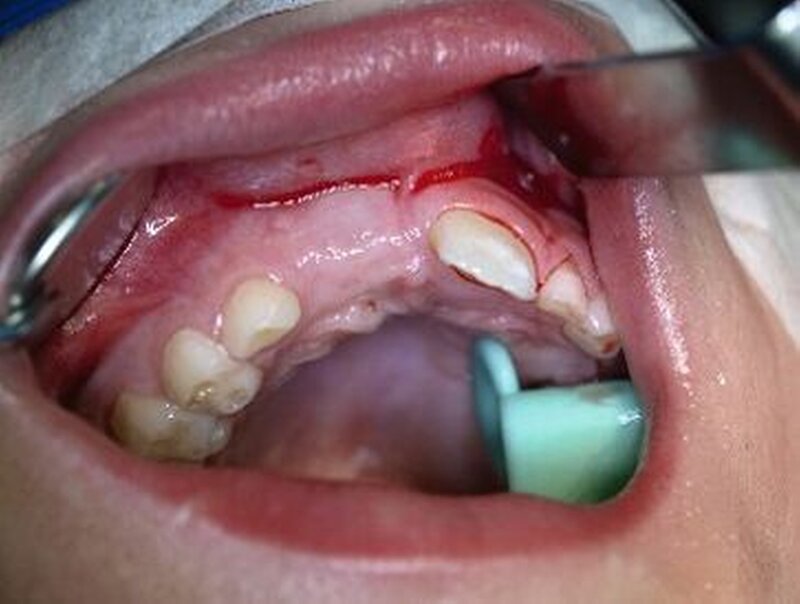

Eine Dekoronation ist eine chirurgische Intervention, die durchgeführt werden kann, wenn aufgrund ausgeprägter Schädigungen der desmodontalen Zellen und der Wurzeloberfläche eine Resorption auftritt. Im Rahmen der klinischen Untersuchung imponiert der betroffene Zahn aufgrund der Ankylose mit einem metallischen (hellen) Klopfschall. Röntgenologisch lassen sich Resorptionslakunen an der Wurzeloberfläche erkennen. Bei progressiver Resorption und Infraposition des betroffenen Zahnes in Relation zur Restdentition kann eine Dekoronation indiziert sein [Malmgren et al., 2015] (Abbildung 2).

Das Ziel der Dekoronation ist es, die klinische Krone unter Belassung der resorbierenden Wurzel zu entfernen, damit der Alveolarknochen aufgrund der Knochenneubildung bei Ersatzresorption erhalten und eine optimale Voraussetzung für spätere Interventionen gegeben werden kann [Malmgren et al., 2006]. Bei Patienten im Wachstum kann die Dekoronation eine sinnvolle Therapieoption darstellen, um den teils erheblichen Knochenverlust in Verbindung mit der chirurgischen Entfernung der ankylosierten Zahnwurzel zu vermeiden (Empfehlung 60).